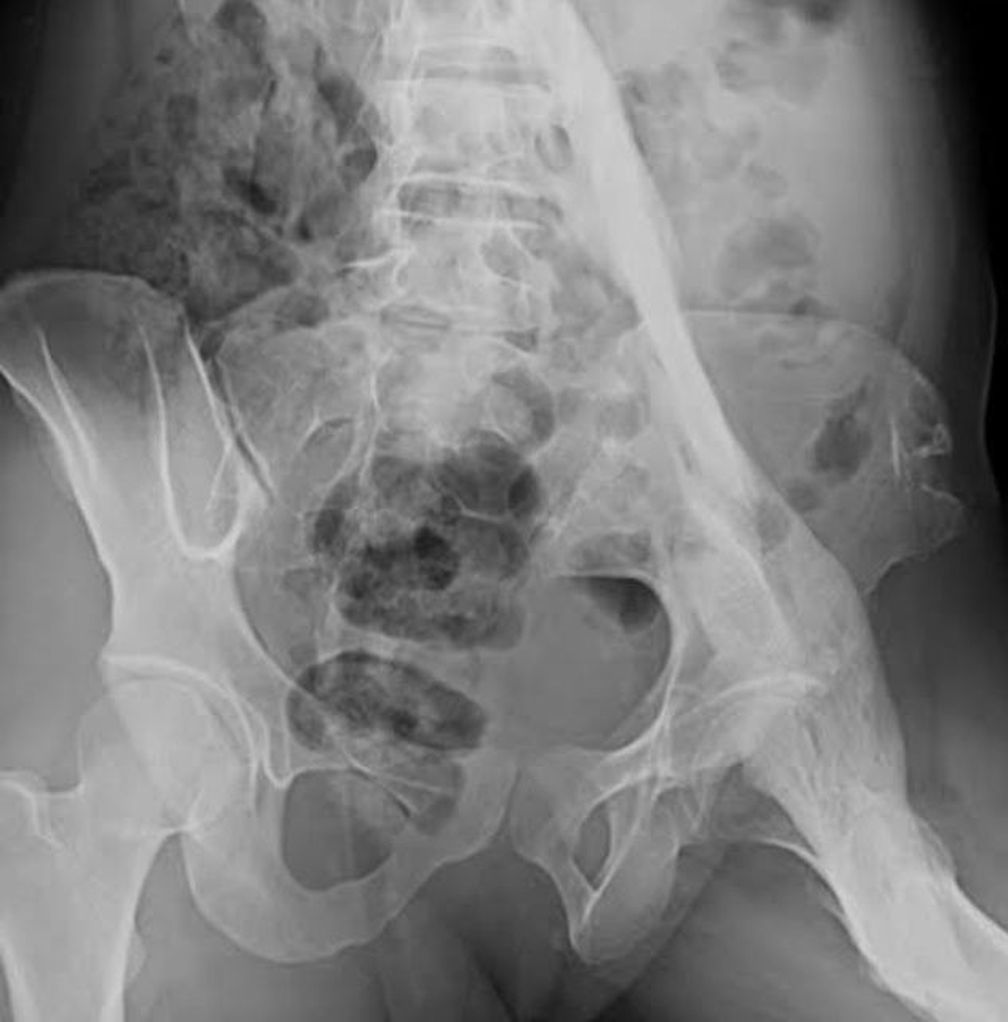

Fibrodysplasia ossificans progressiva (FOP) is a disorder in which skeletal muscle and connective tissue, such as tendons and ligaments, are gradually replaced by bone (ossified). This condition leads to bone formation outside the skeleton (extra-skeletal or heterotopic bone) that restricts movement.